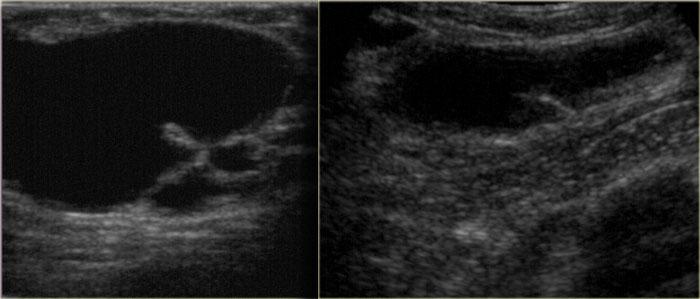

Bên trái là nhũ ảnh và hình siêu âm của một bệnh nhân có gynecomastia thể nốt tuyến.

Lưu ý tổn thương nằm ngay dưới núm vú.

Hình siêu âm cho thấy hình ảnh điển hình của gynecomastia: một khối giảm âm với bờ thùy múi hoặc thậm chí có gai.

Nếu đây là hình ảnh của một phụ nữ, bạn sẽ nhận định đây là một khối có vi thùy múi và gai, tức là Birads IV hoặc V.

Ở nam giới, đây là hình ảnh điển hình của gynecomastia.

Bên trái là cùng hình siêu âm đó, nhưng ở tư thế bình thường.

Lưu ý hình ảnh trông ‘ác tính’ như thế nào.